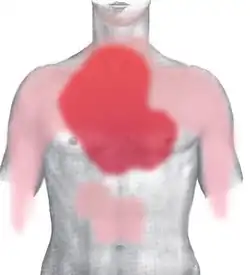

rot: häufig und stark

rosa: selten oder ausstrahlend

Bei der Angina pectoris handelt es sich typischerweise um dumpfe, drückende, einschnürende und häufig brennende Schmerzen, die hinter dem Brustbein (retrosternal) lokalisiert sind. Von den Betroffenen wird der Schmerz häufig als „Engegefühl in der Brust“ beschrieben. Typisch ist außerdem eine Ausstrahlung des Schmerzes in den linken oder seltener in beide Arme. Darüber hinaus können pektanginöse Beschwerden ein atypisches Bild zeigen (atypische Angina pectoris), das heißt, sie können einen anderen Schmerzcharakter sowie eine andere Schmerzlokalisation haben, und sie können in andere Körperregionen (Hals, Unterkiefer, Oberbauch, Rücken) oder überhaupt nicht ausstrahlen. Der Mechanismus, wie es zu einer Schmerzwahrnehmung (Nozizeption) bei Ischämie kommt, ist bisher noch nicht sicher geklärt.